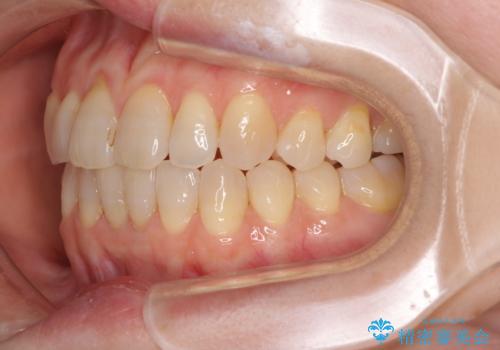

前歯の叢生と切端咬合 インビザラインによる矯正治療

- 前歯のデコボコを気にして来院された患者様です。

上下前歯の先端同士が接触する切端咬合であったため、上顎は歯列を拡大し、下顎はIPR(歯と歯の間を削る)により叢生を解消しながら歯列を小さくすることとしました。

治療前から歯肉退縮が認められ、矯正治療により悪化する可能性が考えられたため、無理のない歯の移動と頻繁な経過観察を行いました。

切端咬合はスムーズに解消され、前歯の負担を軽減させることができました。